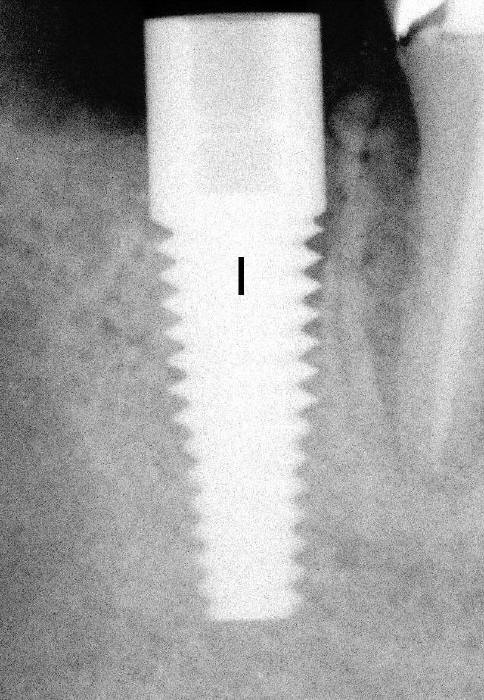

Fig.13: Immediately post-implantation.